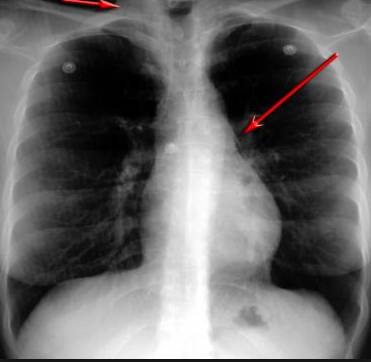

并且,因為呼吸系統(tǒng)結(jié)構(gòu)復(fù)雜,在體檢時醫(yī)生很難通過一種檢測手段,判定早期患者的病情。

使用這臺掃描儀,將直接把器官變成3D圖形!細微的毛細血管,幾毫米大的肺泡和支氣管,都將能看的一清二楚!

你的每一個氣泡,每一段支氣管,哪兒有病變都清清楚楚的將展示在醫(yī)生面前!

也就是說在一切都還沒開始惡化前,把這些有問題的器官組織都暴露的一清二楚:

不同于CT掃描,需要從同一角度,拍下無數(shù)張器官二維圖,從而搭建3D器官結(jié)構(gòu)圖那般費時費力。

4D掃描儀將直接從不同角度,同時對人體器官進行掃描,然后通過計算機算法進行快速成像。CT需要花幾小時才能完成的工作,

4D掃描將在幾秒內(nèi)完成!

當大家還在為B超、X光、CT哪個輻射更少而爭論不休時,這臺新機器已經(jīng)比現(xiàn)有掃描儀少20%的輻射

不需要重復(fù)拍片,輻射也更少!

沒有這項新技術(shù),醫(yī)生在做體檢的時候,很難通過一種測試斷定一個人是否有呼吸系統(tǒng)疾病。

可是現(xiàn)在他們不但能看到整個肺部的3維結(jié)構(gòu)圖。還能看到空氣進入人體后的所有微小變動!